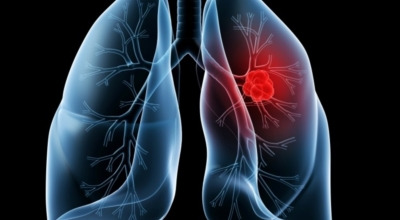

폐에 발생한 악성 종양을 말하며, 오랜 기간 흡연해온 남성에게서 발병률이 높습니다. 하지만 최근에는 다양한 환경적 요인과 간접흡연의 영향으로 흡연하지 않는 여성에게서도 많이 발생하고 있답니다. 증상을 느껴 병원을 찾았을 때는 이미 수술하기엔 늦은 경우가 많아 사망률이 매우 높은 암입니다. 폐 자체에서 생기거나 다른 장기에서 발생한 암이 폐로 전이되어 나타나기도 하며, 특별한 초기 증상이 없는 경우가 많습니다. 암이 진행된 후에도 일반적인 감기 증상인 기침과 가래 외에 뚜렷한 증상이 나타나지 않아, 증상만으로는 진단이 쉽지 않습니다.

폐암 검사는 주로 X-ray를 통해 이루어지지만, 종양의 크기가 작거나 구석에 위치한 경우에는 확인이 어려운 경우도 있습니다. 그 후, 조직 검사를 통해 정확한 진단을 하게 됩니다. 폐암이 발견되면, 종양의 크기, 전이 여부, 위치에 따라 수술 여부를 결정하게 됩니다.